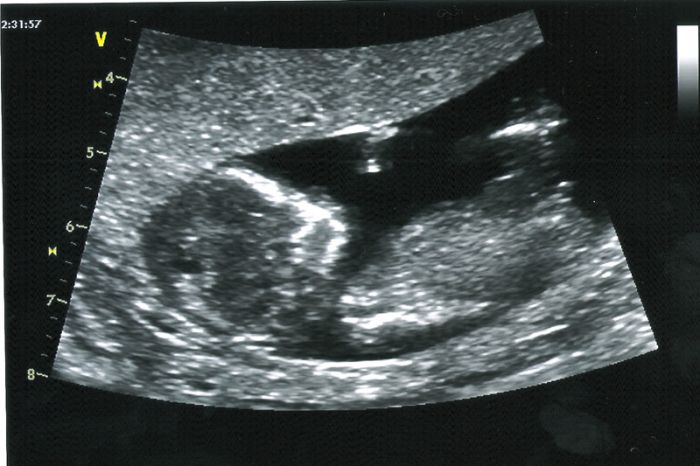

Ahoj holky, všem moc moc děkuji za držení palců:0) Screening dopadl nad očekávání dobře :) jen jsem teď hrozně unavená a trochu bříško bolí, protože se druhej prcek nechtěl moc ukázat :) A v jednu chvíli jsem to zabojkotovala já, protože jak paní doktorka zaryla ultrazvukem do bříška - tak bylo vidět, jak malej do něj buší ručičkou :0)) což sem neustála a vyprskla smíchy :0)))Od pondělka pěkně povyrostli - jeden 55mm a druhý 58mm - tp 25.2. Pohlaví nevíme, ale zatím vše vyšlo tak, že nemusíme ani na plodovku, což vůbec nikdo nečekal, že by mohlo vyjít takhle dobře v mém věku :0) Jsem šťastná jak blecha :) Tak teď ještě počkat až se holky vrátí taky se skvělými výsledky :0))) Moc jim držím palce:)

Holky taky vám moc děkuji za podporu.. Nespala jsem dneska od půl páté ráno a dopoledne už jsem byla tak vystresovana, protože už třetí den mám zácpu, že jsem si i pobrečela.. Na screening jsme jeli na půl druhé a všechno dopadlo na vybornou.. :)) mám radost.. :) přítel z toho byl taky nadšený.. Jak se tam malý hybal.. Srdíčko krásně tkouklo.. :) a jak jsme se vrátili, tak jsme to oznámili mojí rodině a ti byli překvapeni ale příjemně.. :)) teď si to konečně začnu užívat.. :)

Assi nádherný fotky obou mrňousků. Je jim u tebe dobře, tak rostou jako z vody